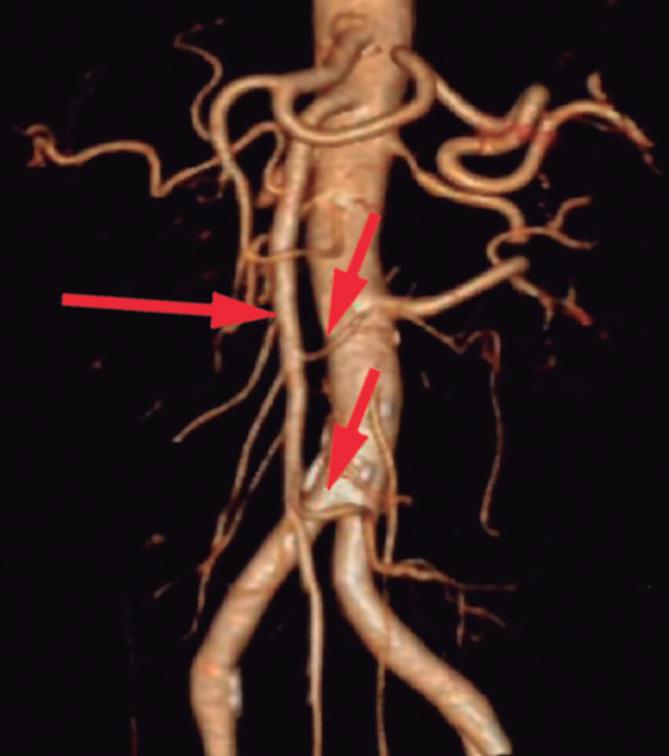

Páncreas Circumportal

El páncreas engloba a la vena mesentérica superior o vena porta, en lugar de rodear al duodeno como sucede en el páncreas anular (Figura 14). Tiene una prevalencia de hasta 2,5% según algunas series, por ende, no es tan infrecuente encontrarlo en estudios por imágenes. Se

A B

postula que su origen está relacionado con una anomalía en la rotación y fusión del brote ventral con el dorsal. Es una condición asintomática, pero cobra relevancia reconocerla e informarla en pacientes que serán sometidos a cirugía del páncreas, con el fin de reducir complicaciones, particularmente la fístula pancreática.25, 26